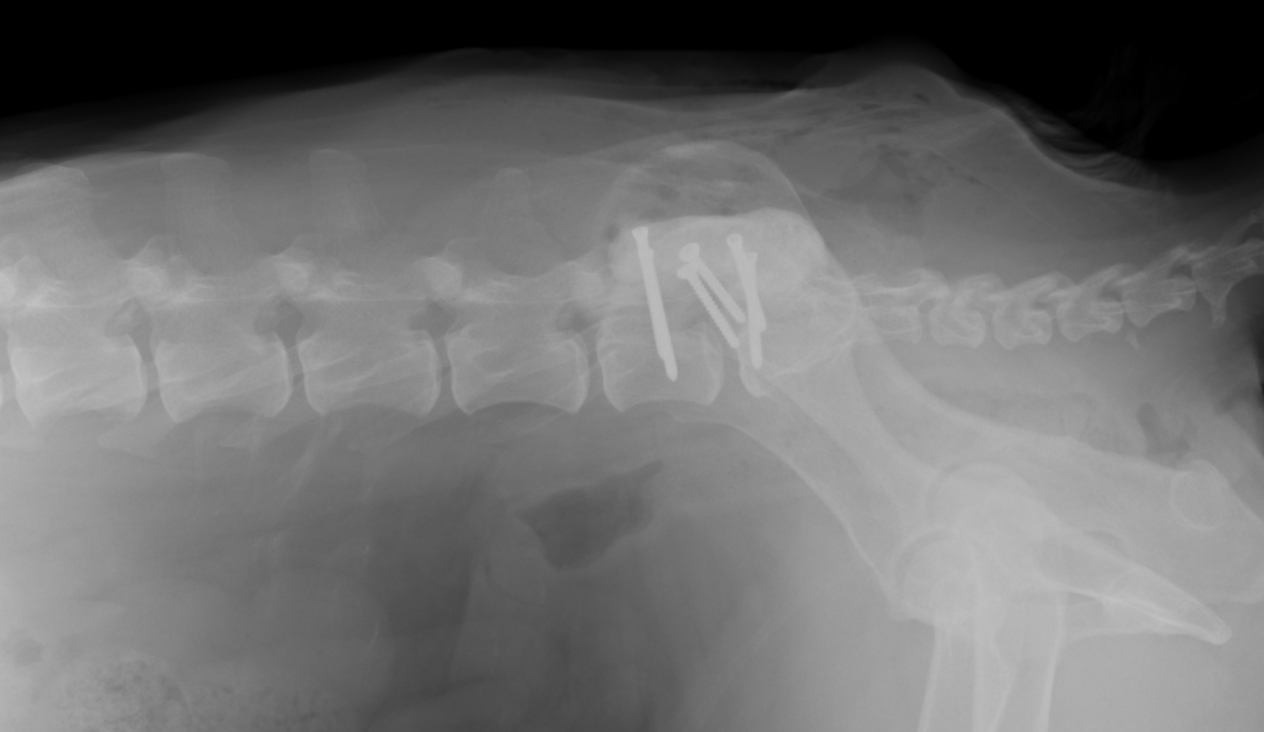

背側からラウンドバーと呼ばれる機械で削り、中に見えてくる黄色靭帯を摘出していきます。圧迫が解除されたらスクリューをうち、セメントによって固定します。

スクリューとセメントで固定されています。